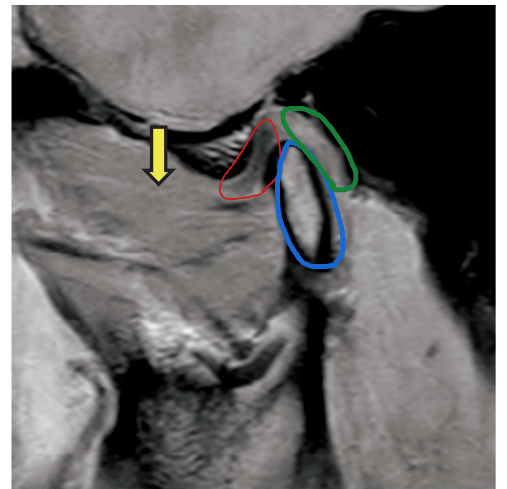

顎関節部 MRI(別冊No. 1)を別に示す。

矢印で示すのはどれか。 1 つ選べ。

解答:d

解説:

赤:関節円板

青:下顎頭

緑:関節円板後部組織

黄色の矢印:外側翼突筋